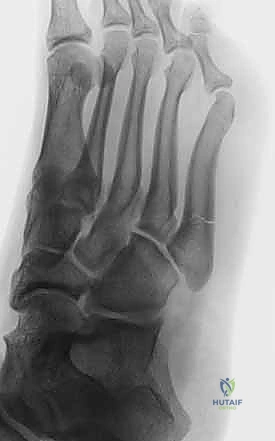

Radiographic Assessment

Standard weight-bearing (if tolerated) anteroposterior, lateral, and oblique radiographs of the foot are mandatory. The oblique view profiles the fifth metatarsal base optimally, allowing for clear visualization of the fracture line and assessment of the fourth-fifth intermetatarsal joint.

The surgeon must carefully evaluate the radiographs for signs of chronicity (Torg Type II or III), such as cortical thickening, widening of the fracture gap, and medullary canal sclerosis. If a diaphyseal stress fracture or nonunion is suspected but radiographically ambiguous, Advanced imaging with Computed Tomography (CT) can precisely delineate the extent of canal sclerosis, while Magnetic Resonance Imaging (MRI) is highly sensitive for detecting early stress reactions before cortical fracture occurs.

Clinical & Radiographic Imaging